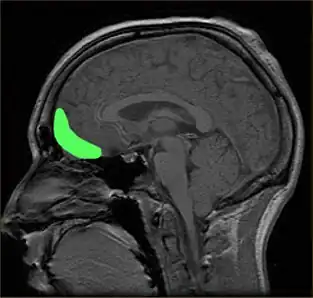

- Boldness. Low fear including stress-tolerance, toleration of unfamiliarity and danger, and high self-confidence and social assertiveness. The PCL-R measures this relatively poorly and mainly through Facet 1 of Factor 1. Similar to PPI fearless dominance. May correspond to differences in the amygdala and other neurological systems associated with fear.[1][4]

- Disinhibition. Poor impulse control including problems with planning and foresight, lacking affect and urge control, demand for immediate gratification, and poor behavioral restraints. Similar to PCL-R Factor 2 and PPI impulsive antisociality. May correspond to impairments in frontal lobe systems that are involved in such control.[1][4]

Dysfunctions in the prefrontal cortex and amygdala regions of the brain have been associated with specific learning impairments in psychopathy. Since the 1980s, scientists have linked traumatic brain injury, including damage to these regions, with violent and psychopathic behavior. Patients with damage in such areas resembled "psychopathic individuals" whose brains were incapable of acquiring social and moral knowledge; those who acquired damage as children may have trouble conceptualizing social or moral reasoning, while those with adult-acquired damage may be aware of proper social and moral conduct but be unable to behave appropriately. Dysfunctions in the amygdala and ventromedial prefrontal cortex may also impair stimulus-reinforced learning in psychopaths, whether punishment-based or reward-based. People scoring 25 or higher in the PCL-R, with an associated history of violent behavior, appear to have significantly reduced mean microstructural integrity in their uncinate fasciculus—white matter connecting the amygdala and orbitofrontal cortex. There is evidence from DT-MRI of breakdowns in the white matter connections between these two important areas.[121][122][123]

Researchers have linked head injuries with psychopathy and violence. Since the 1980s, scientists have associated traumatic brain injury, such as damage to the prefrontal cortex, including the orbitofrontal cortex, with psychopathic behavior and a deficient ability to make morally and socially acceptable decisions, a condition that has been termed "acquired sociopathy", or "pseudopsychopathy".[130] Individuals with damage to the area of the prefrontal cortex known as the ventromedial prefrontal cortex show remarkable similarities to diagnosed psychopathic individuals, displaying reduced autonomic response to emotional stimuli, deficits in aversive conditioning, similar preferences in moral and economic decision making, and diminished empathy and social emotions like guilt or shame.[144] These emotional and moral impairments may be especially severe when the brain injury occurs at a young age. Children with early damage in the prefrontal cortex may never fully develop social or moral reasoning and become "psychopathic individuals ... characterized by high levels of aggression and antisocial behavior performed without guilt or empathy for their victims". Additionally, damage to the amygdala may impair the ability of the prefrontal cortex to interpret feedback from the limbic system, which could result in uninhibited signals that manifest in violent and aggressive behavior.[121][132]

A 2008 review by Weber et al. suggested that psychopathy is sometimes associated with brain abnormalities in prefrontal-temporo-limbic regions that are involved in emotional and learning processes, among others.[154] Neuroimaging studies have found structural and functional differences between those scoring high and low on the PCL-R in a 2011 review by Skeem et al. stating that they are "most notably in the amygdala, hippocampus and parahippocampal gyri, anterior and posterior cingulate cortex, striatum, insula, and frontal and temporal cortex".[4][155]

The amygdala and frontal areas have been suggested as particularly important.[122] People scoring 25 or higher in the PCL-R, with an associated history of violent behavior, appear on average to have significantly reduced microstructural integrity between the white matter connecting the amygdala and orbitofrontal cortex (such as the uncinate fasciculus). The evidence suggested that the degree of abnormality was significantly related to the degree of psychopathy and may explain the offending behaviors.[123] Furthermore, changes in the amygdala have been associated with "callous-unemotional" traits in children. However, the amygdala has also been associated with positive emotions, and there have been inconsistent results in the studies in particular areas, which may be due to methodological issues.[4]

Some of these findings are consistent with other research and theories. For example, in a neuroimaging study of how individuals with psychopathy respond to emotional words, widespread differences in activation patterns have been shown across the temporal lobe when psychopathic criminals were compared to "normal" volunteers, which is consistent with views in clinical psychology. Additionally, the notion of psychopathy being characterized by low fear is consistent with findings of abnormalities in the amygdala, since deficits in aversive conditioning and instrumental learning are thought to result from amygdala dysfunction, potentially compounded by orbitofrontal cortex dysfunction, although the specific reasons are unknown.[132][156]

Considerable research has documented the presence of the two subtypes of primary and secondary psychopathy.[157][158] Proponents of the primary-secondary psychopathy distinction and triarchic model argue that there are neurological differences between these subgroups of psychopathy which support their views.[159] For instance, the boldness factor in the triarchic model is argued to be associated with reduced activity in the amygdala during fearful or aversive stimuli and reduced startle response, while the disinhibition factor is argued to be associated with impairment of frontal lobe tasks. There is evidence that boldness and disinhibition are genetically distinguishable.[4]